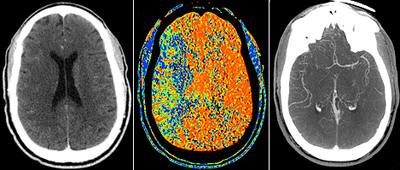

There are many benefits for patients from medical imaging. Images of the human body are created using a variety of means such as ultrasound, magnetic resonance, nuclear medicine and X-rays to allow physicians to see inside the body, to identify and/or rule out medical problems, and to diagnose diseases. Much has recently been written about radiation, so it is important to have some understanding of imaging performed using radiation, especially the benefits to the patient along with the associated risks.

Keep in mind that the radiation doses used in medical radiological imaging examinations like computed tomography (CT) and X-ray scans are much lower than those used in radiation oncology, which uses radiation as a therapy to treat cancer. Radiology (imaging) and radiotherapy (cancer treatment) are quite different.

The modern use of imaging has been one of the great advances made in the practice of medicine, allowing doctors to diagnose and manage their patients’ diseases safely and rapidly. Many of today’s medical improvements require tests using radiation to confirm diagnoses, plan management, and monitor the response to treatment.

Most people in the United States have benefited by imaging, whether from a simple chest X-ray for a cough, a bone X-ray for a fracture, or something more complex like a CT scan. The discovery of X-rays in 1895 by Wilhelm Roentgen led to the first Nobel Prize in Physics. CT ranks as one of the top five medical developments in the last 40 years, according to most medical surveys. It has proven so valuable as a medical diagnostic tool that the 1979 Nobel Prize in Medicine was awarded to the inventors of CT.